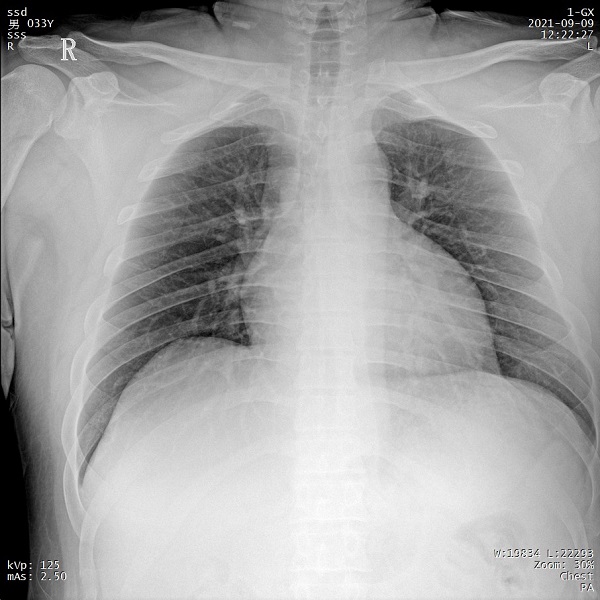

二、1ms 短時曝光 定格心肺運動瞬間影像

PLX5500能夠在最短1ms的曝光時間內(nèi)輸出足量的X射線,獲取清晰圖像。特別適用于拍攝肺炎、塵肺病、肺結(jié)核等難以憋氣的患者,避免了因患者肺部呼吸運動而產(chǎn)生的運動偽影的影響,瞬間定格清晰圖像,以供醫(yī)生精確診斷。